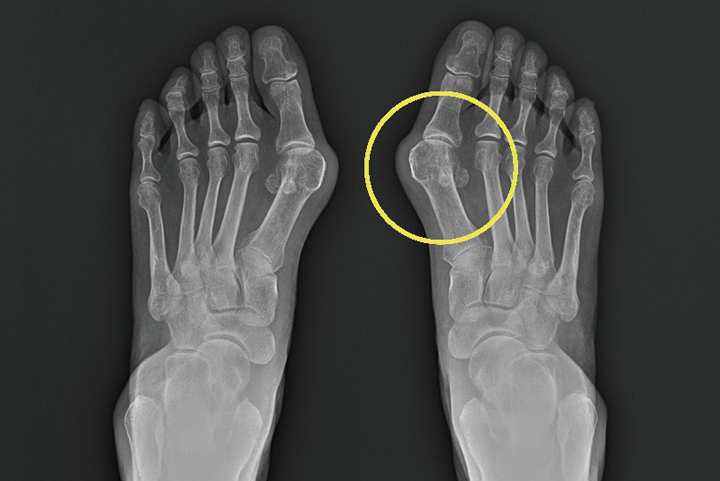

방사성 진단

Standing 전후면, 측면, 사면 사진 촬영하여 족무지 외반각이 15도 이상, 중족골간 각이 9도 이상이면 진단할 수 있습니다.무지외반증 치료